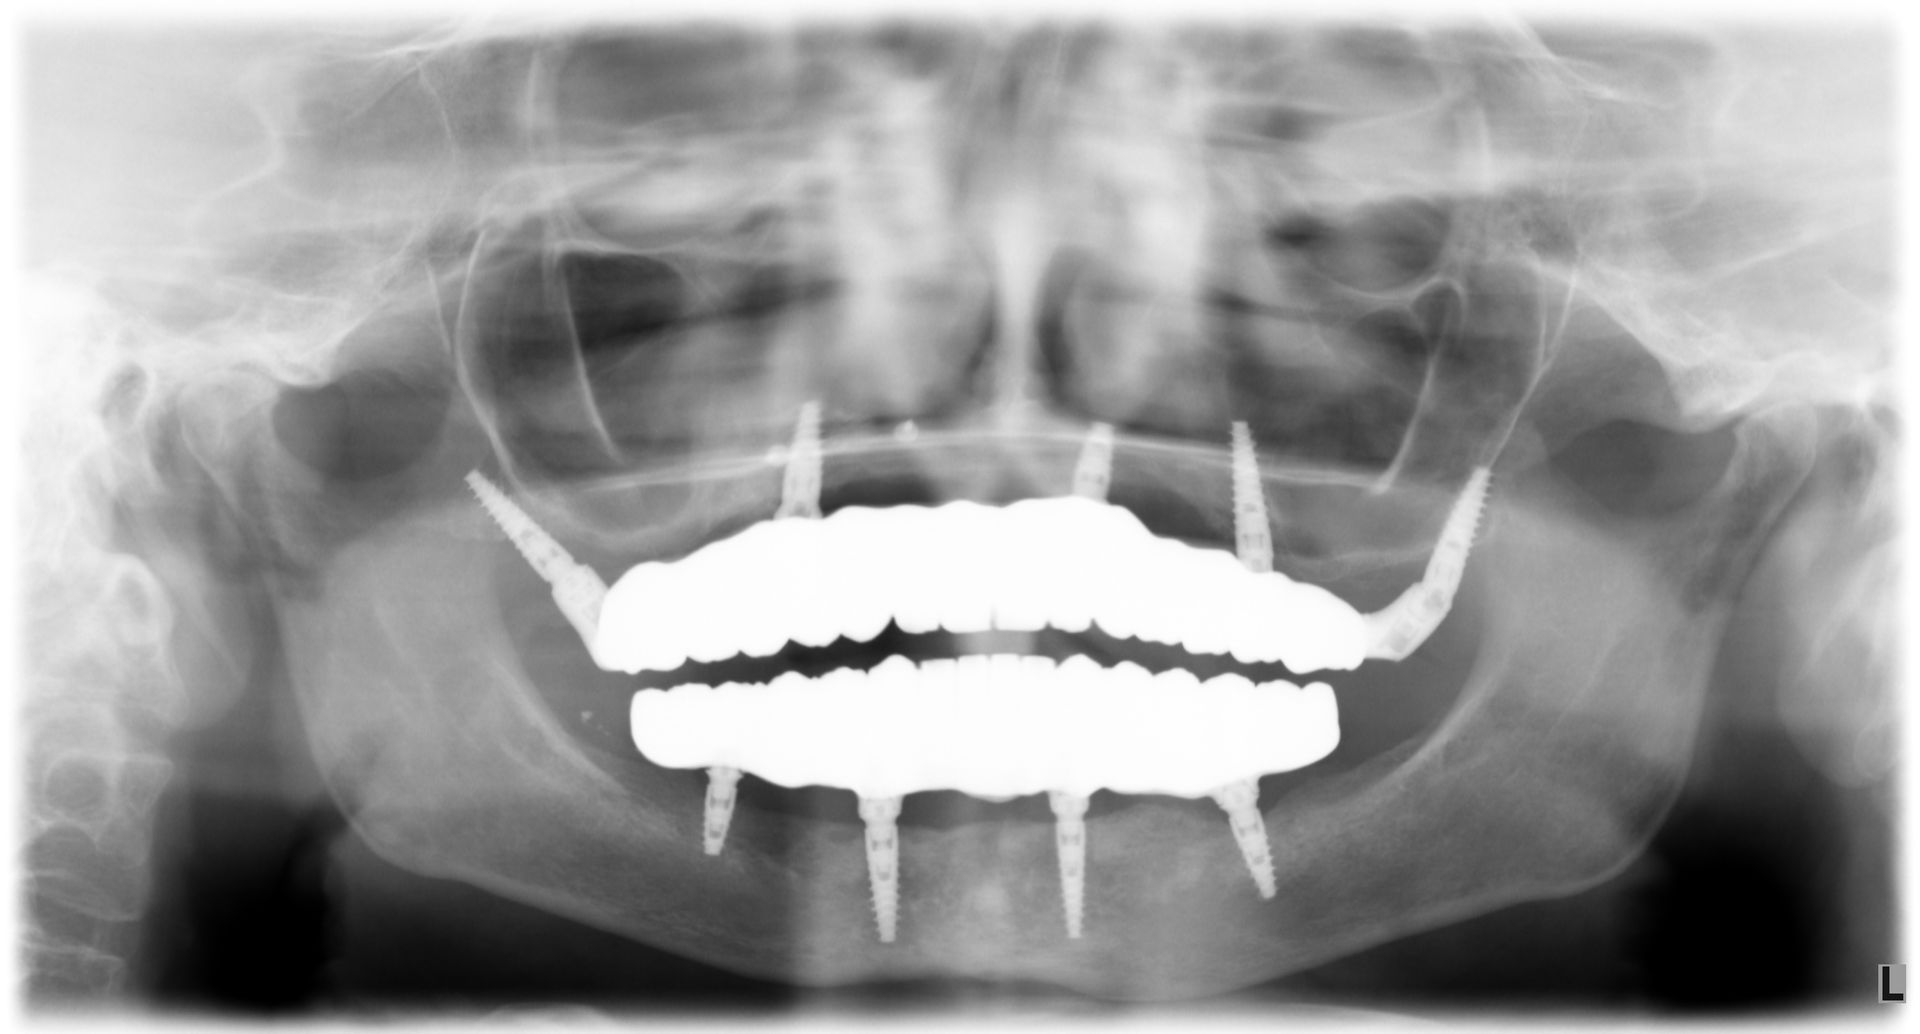

Vedi il caso qui accanto il paziente aveva vecchi impianti falliti e una protesi totale superiore e gli avevano detto che non aveva possibilità di mettere denti fissi...

ecco il caso completo

Il paziente era molto amareggiato perché non tollerava la protesi totale e aveva dolori dovuti agli impianti infetti dell'arcata inferiore. Dopo un attento studio del caso, in cui sono state studiate le forme e le altezze delle nuove protesi e abbiamo eseguito una pianificazione digitale dell'intervento chirurgico impiantare abbiamo inserito 5 impianti nel superiore con una rigenerativa orizzontale e 4 impianti nell'inferiore. a distanza di 4 ore dall'intervento abbiamo caricato gli impianti con le protesi provvisorie a carico immediato fatte con resina e una struttura in titanio, a distanza di 6 mesi sono state sostituite con 2 arcate titanio zirconio.